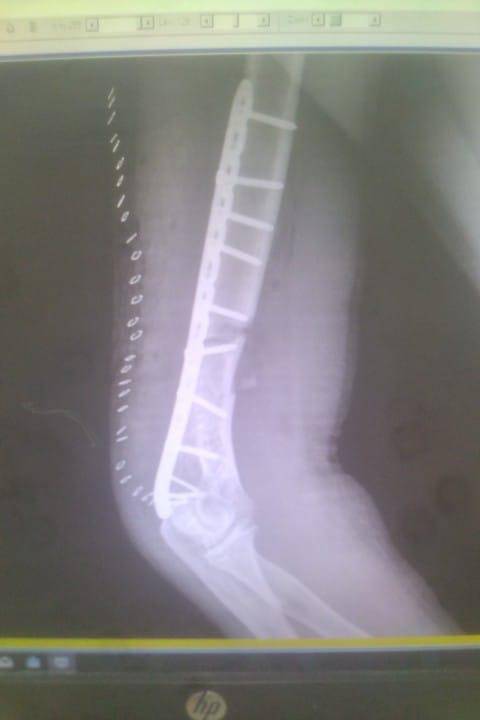

- إجراء عمليات جراحية معقدة و دقيقة في مجال العظام و المفاصل و الكسور و الإصابات ، رغم الضغط الكبير على المستشفى و أعداد المراجعين الكبيرة.

- تطبيق تقنيات جراحية حديثة و متقدمة، و ذلك في ظل التحديات التي يواجهها الفريق بسبب أعداد المرضى و المراجعين الكبيرة.

- تقديم خدمات جراحية عالية الجودة و آمنة للمرضى، رغم الضغط الهائل على المستشفى في العيادة و القسم و الطوارئ .